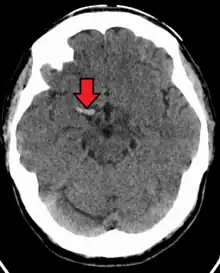

Cerebral venous sinus thrombosis (CVST) is a rare form of stroke which results from the blockage of the dural venous sinuses by a thrombus. Symptoms may include headache, abnormal vision, any of the symptoms of stroke such as weakness of the face and limbs on one side of the body and seizures. The diagnosis is usually made with a CT or MRI scan. The majority of persons affected make a full recovery. The mortality rate is 4.3%.[8]